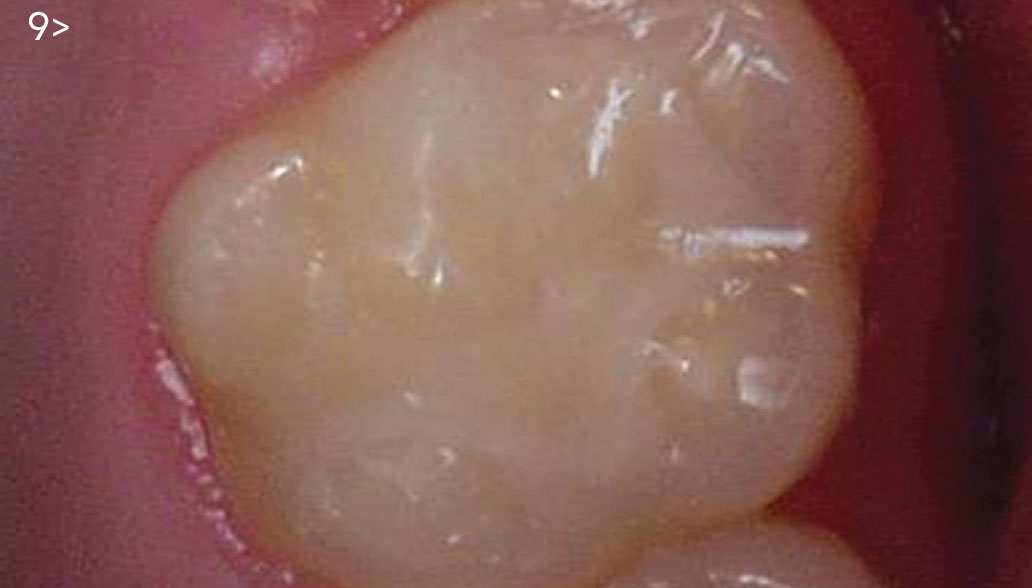

- Fig. 8: Resin-based composite being incrementally placed on top of the direct pulp cap.

- Fig. 9: Restoration at 3-year follow-up.

Subsequent follow-up appointments revealed no sensitivity

or complications (Fig. 9). Routine radiographic and clinical examination

has been provided for the last 3 years.